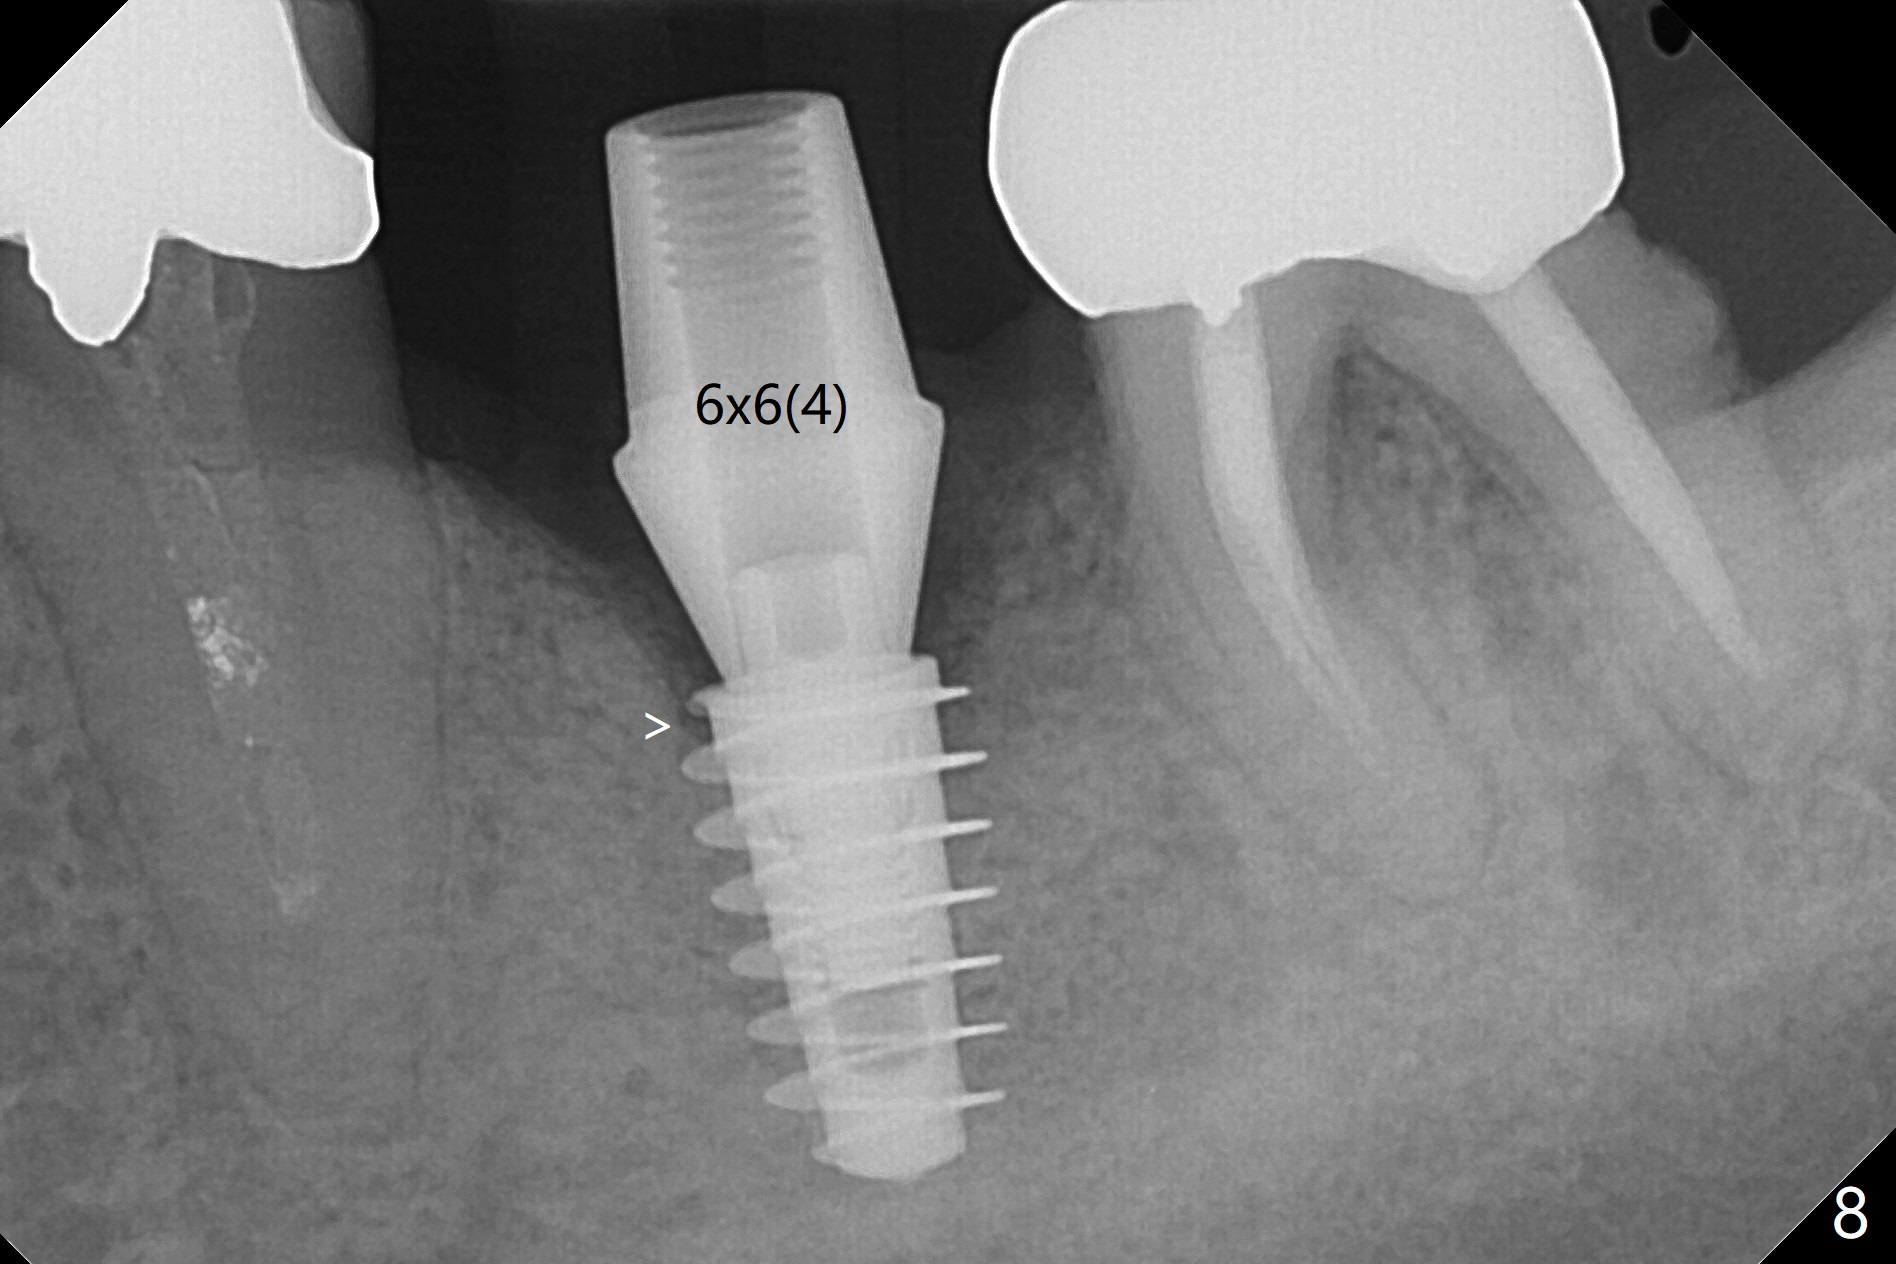

When the patient returns 4 months post implant removal and bone graft, the ridge at #19 is concave with a small hole which communicates with the underlying bone (Fig.1 <). The low density bone in the middle of the socket is ignored (Fig.2 *, 3 S (soft)). With under drilling, primary stability of tissue-level taps is lower. A bone-level dummy implant is placed with low torque (Fig.4). After removal of granulation tissue distal to the osteotomy, a larger implant is inserted with ~15 Ncm; mixture of autogenous bone and allograft is packed (Fig.5 *). The latter is covered by 12x12 mm BioXclude and sutured with 4/0 Chromic Gut tension free. 植牙后6.5月牙槽嵴饱满,角化龈宽(图六(刚开始浸润麻醉))。术后6.5月切开证实植体上面没有骨质覆盖(如图七:*),第一螺纹可能暴露(>)。由于骨质吸收,大号基台置入没阻挡,或者困难(图八),第一螺纹暴露(>)需要再次植骨(图九:*)。放置大号基台(6x6(4)毫米)和植骨使萎缩牙槽嵴部分得到修复(图十,与Uncover前(图六)对比)。Uncover时即刻置入修复性基台好处是利用基台牙龈外部分强化牙周敷料固定,基台中央放置一个棉球后,敷料可以插入基台中央进一步增加固位(图十一(舌侧观):*)。